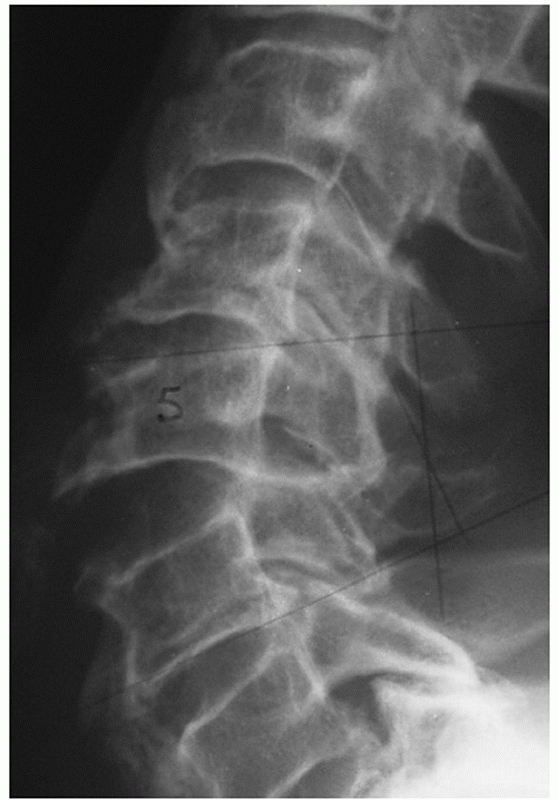

characteristics can be assessed and measured on a lateral cervical

film. Segmental kyphosis can be measured by an endplate (Cobb) method

or posterior vertebral body tangent method (Figs. 42-8 and 42-9).

The latter may have lower interobserver variability. Kyphosis more than

11 degrees as measured by the endplate method is strongly suggestive of

posterior ligamentous injury and potential instability.248

Kyphosis can be the result of posterior widening of the interspinous

processes and facet joints about an injury axis of rotation near the

ALL. Vertebral body fracture with height loss and interspinous gapping

suggests an injury axis of rotation about the facet joints.